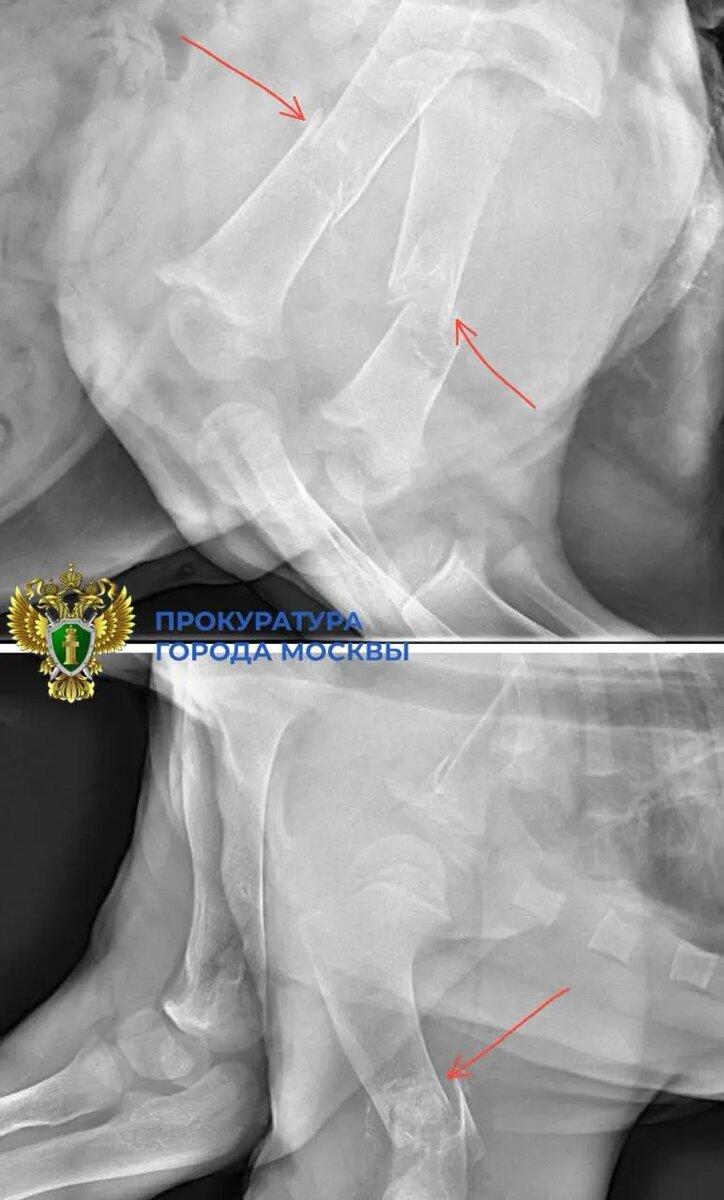

Искалеченного львенка со сломанными лапами изъяли у лакшери-блогера из квартиры в «Москва Сити». Об этом сообщили в пресс-службе столичной прокуратуры. 25 декабря блогер-миллионер сам передал маленькую львицу волонтерам. Животному только 2,5 месяца. Ветеринары получили его в критическом состоянии. У львенка были переломаны три лапы и поврежден позвоночник. Также специалисты выявили общее истощение костной ткани, которое, вероятно, было вызвано ненадлежащими условиями содержания и питания. Сейчас проводится проверка по статье 245 УК РФ («Жестокое обращение с животными»). Сам львенок на реабилитации. Как сообщает телеканал Рен ТВ, блогер размещал в своих соцсетях фото львицы на фоне машин, сумок с деньгами и элитной недвижимости. Позже у животного начались проблемы с костями. Со слов специалистов, они «почти прозрачны», то есть очень хрупки. Хозяин львенка пояснил, что купил его по объявлению. Он утверждает, что такие предложения о покупке экзотических животных совсем не редкость, и прио

25 декабря блогер-миллионер сам передал маленькую львицу волонтерам. Животному только 2,5 месяца. Ветеринары получили его в критическом состоянии. У львенка были переломаны три лапы и поврежден позвоночник. Также специалисты выявили общее истощение костной ткани, которое, вероятно, было вызвано ненадлежащими условиями содержания и питания.

Как сообщает телеканал Рен ТВ, блогер размещал в своих соцсетях фото львицы на фоне машин, сумок с деньгами и элитной недвижимости. Позже у животного начались проблемы с костями. Со слов специалистов, они «почти прозрачны», то есть очень хрупки.